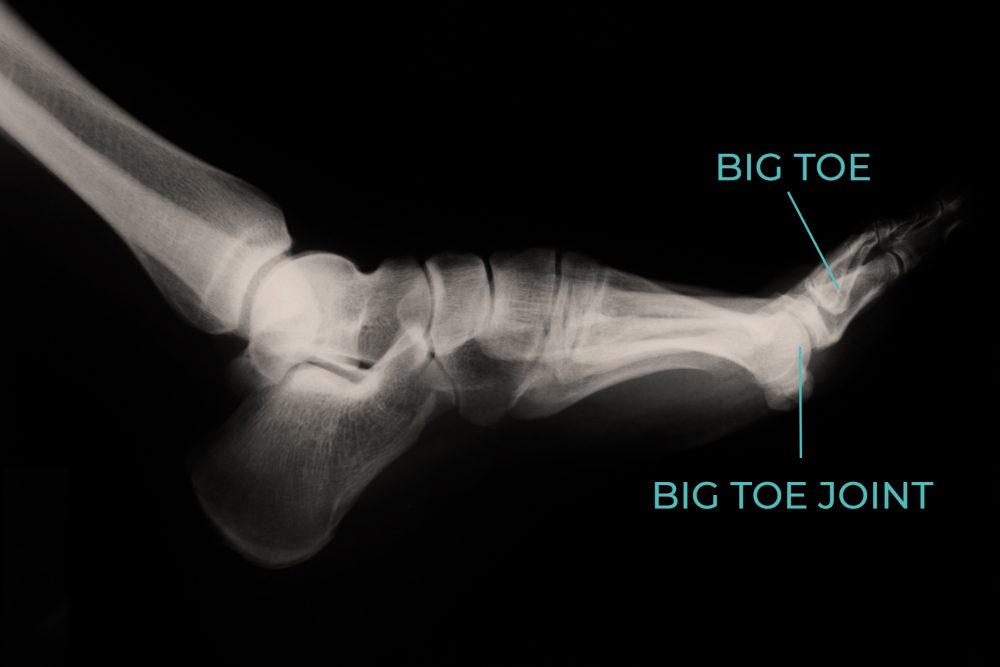

turf toe (a sprain of the metatarsophalangeal joint) is a condition that results from acute or chronic.   the aim of this simple sports taping technique is to prevent excessive bending back (hyperextension) of the big. Place a cloth between your skin and the ice pack to help prevent ice burn.  kt tape provides full support and can help reduce pain for turf toe.   turf toe happens when you bend your big toe up toward the top of your foot too far. Wrap your toe and foot with an elastic bandage to support and reduce swelling. This can cause you to sprain or injure your toe and the. Apply ice for 20 minutes at a time, up to once an hour. Find athletic and foot kinesiology tape plus learn turf toe taping techniques here. Prop your foot above the level of your heart to help decrease swelling.